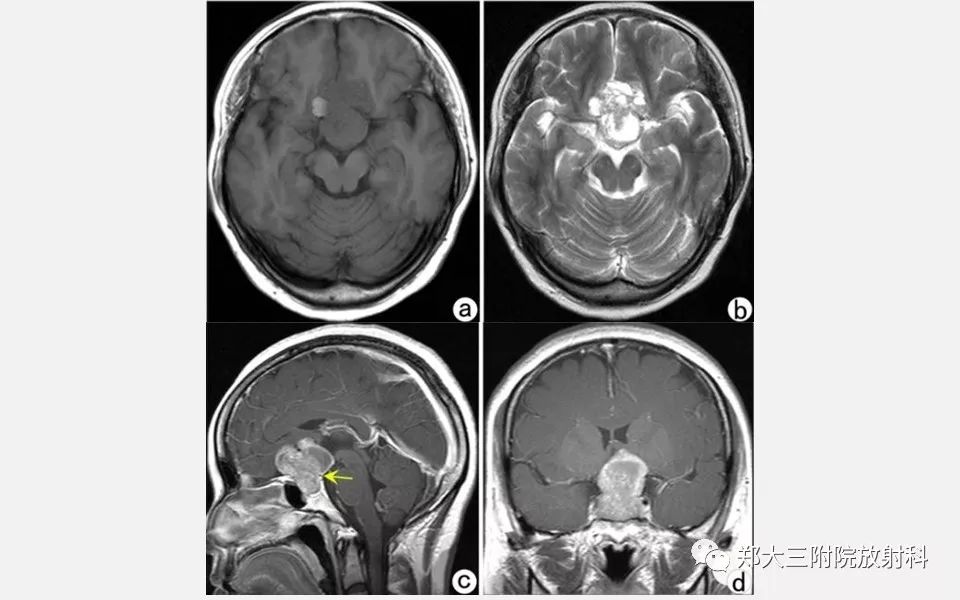

垂体增生的影像表现

【PPT】垂体增生的影像表现